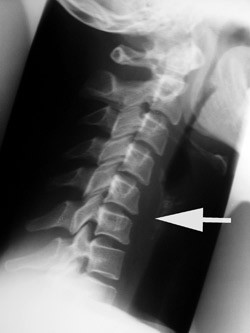

At selv en dokumentert, eldre skade kan være uten symptomer, skulle være velkjent. At de degenerative forandringene progredierer likeså. Og – ja visst – det går svært langsomt, for osteogenesen er en sendrektig prosess, og ofte synes ikke nydanningene – forårsaket av en periostal reaksjon – før etter 5 – 10 år. Jeg vedlegger eksempelvis to bilder av en pasient, tatt med sju års mellomrom. Vedkommende hadde nakkesmerter, men benektet traume, inntil et fall noen måneder tidligere ble nevnt. Det første bildet (fig 1) ble beskrevet som «normalt», tross kyfotisk knekk og antydet skivereduksjon C5 – 6 (pil). Det andre bildet (fig 2) viser resultatet av denne «ubetydelighet», den gang med atskillige plager, i dag med tilnærmet symptomfrihet – dog med langtkommet spondylose og ytterligere reduksjon av skiven.